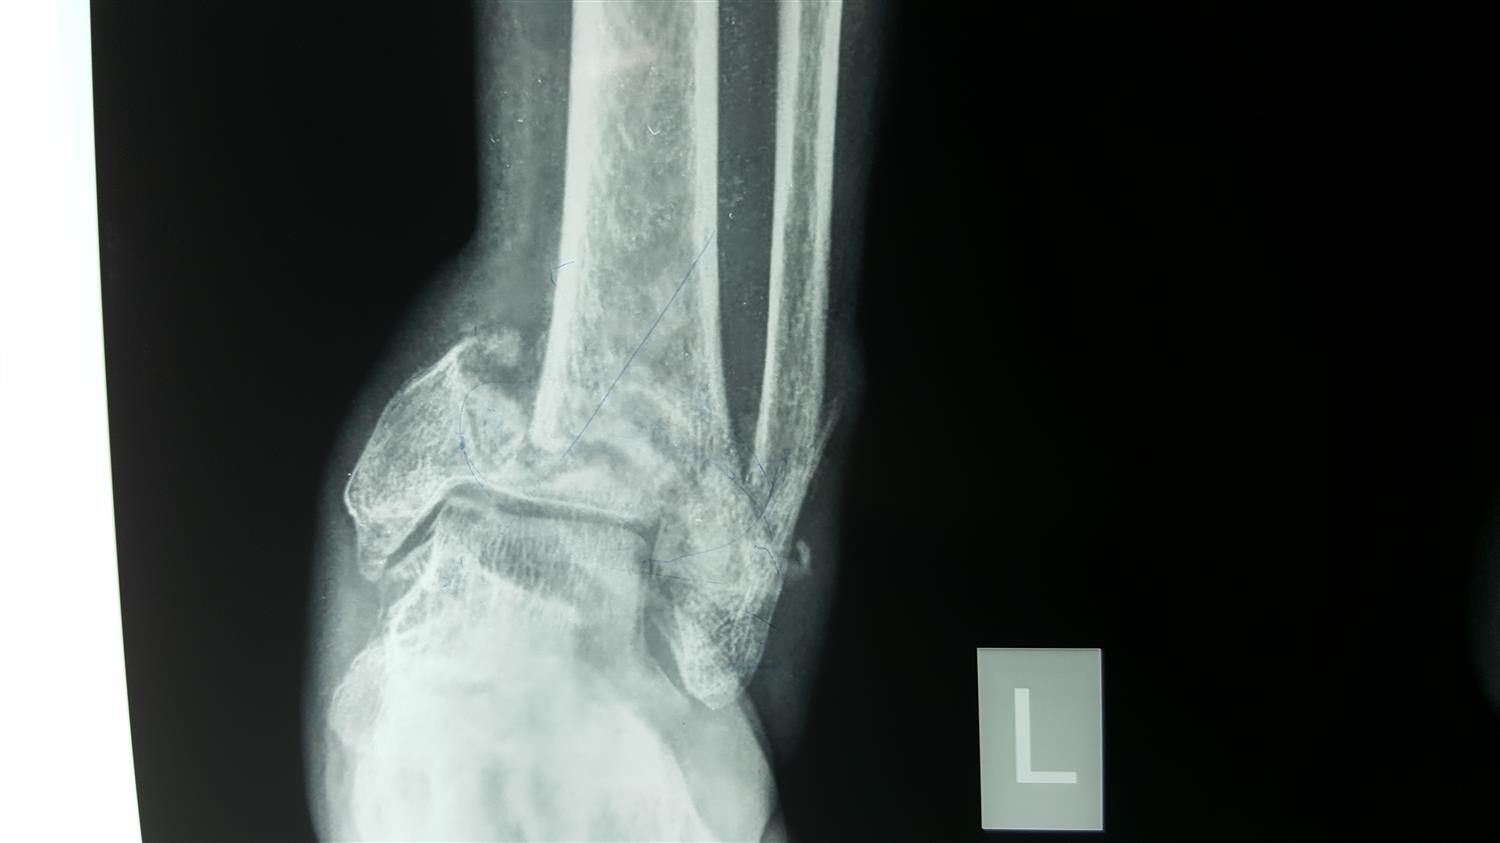

From meds.queensu.ca

Isolated posterior malleolus fracture Posterior Malleolus Fracture Splint 1 as life expectancy continues to. learn about the anatomy, classification, and treatment of lateral malleolus fractures, which are common. ankle fractures are one of the most common lower extremity injuries with an incidence of approximately 179 per 100,000 people a year. there are three main splinting options for the ankle. The most stable splint is the. Posterior Malleolus Fracture Splint.